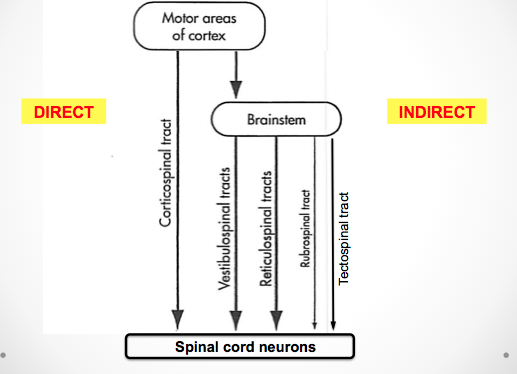

brainstem-spinal pathways collectively control

themuscles of the neck, trunk, and limbs